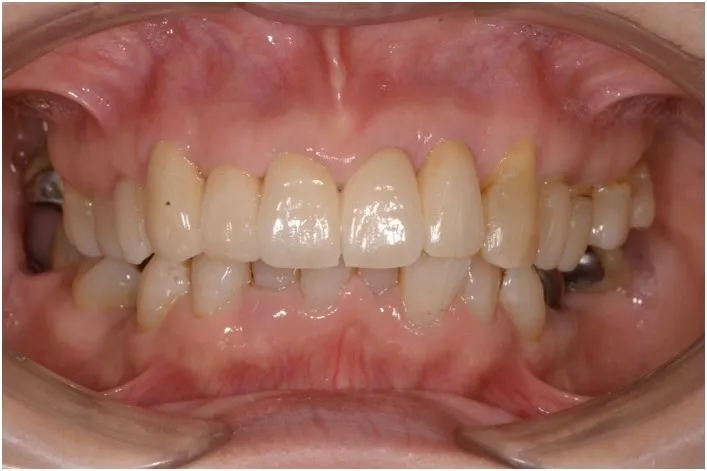

【治療後】